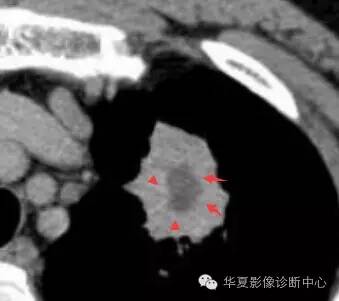

大家仔细看看这个中央不强化的腔内壁

你会发现内壁强化明显,边界清楚

一般这是炎性的脓腔,内层是肉芽肿,明显强化,分界清楚

癌肿的坏死一般是缺血性的,是肿瘤生长速度过快,中央带的血管受挤压,中央供血不足坏死的,一般边界模糊

内有内层强化,不会这么清楚

这是两者坏死的差异

内带强化带,边界清楚

但是这个其实整体看起来不是分叶征

只是一个一个的凸起